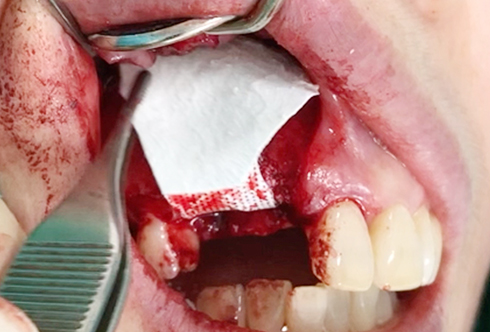

A surgical procedure using resorbable membrane

• A surgical procedure using resorbable membrane 1